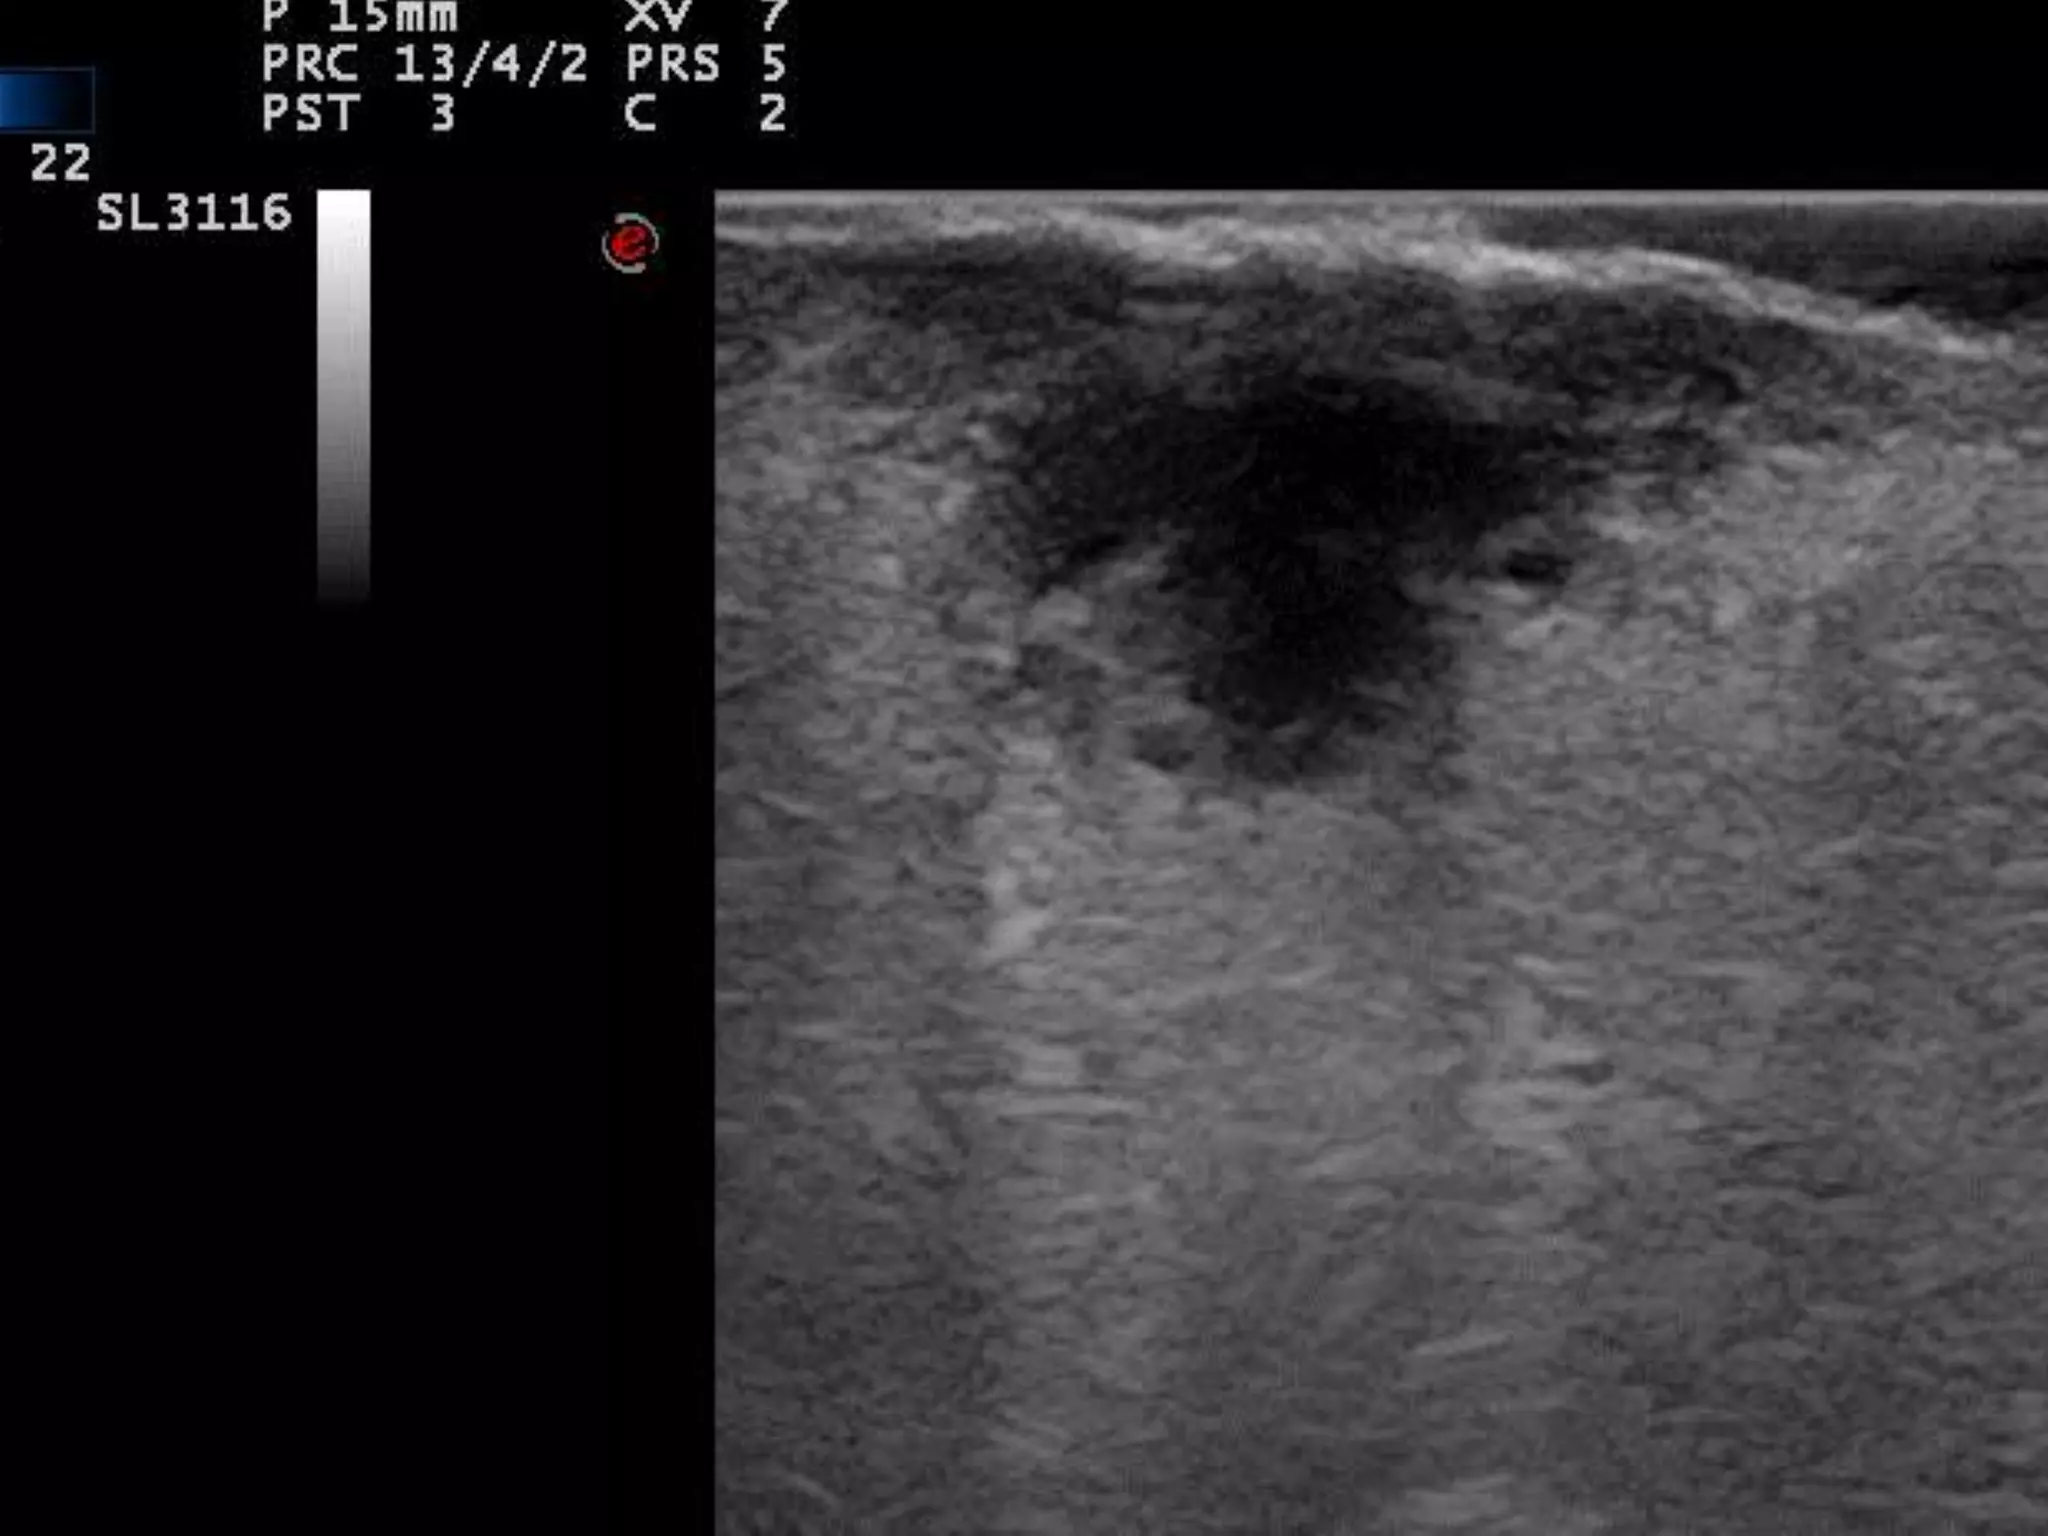

LOCALIZACION DE INFLAMACION

FOLICULAR

TINEA CAPITIS